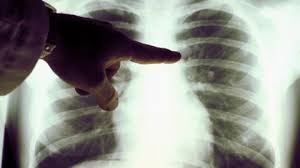

Legionellose Radio Pulmonaire : 1 / Il peut être localisé à une partie du poumon ou s'étendre à l'ensemble de l'appareil pulmonaire.

Face aux symptômes qui évoquent une pneumopathie interstitielle, le médecin va tout d'abord prescrire une radio des poumons, qui met en évidence un épaississement du tissu interstitiel.